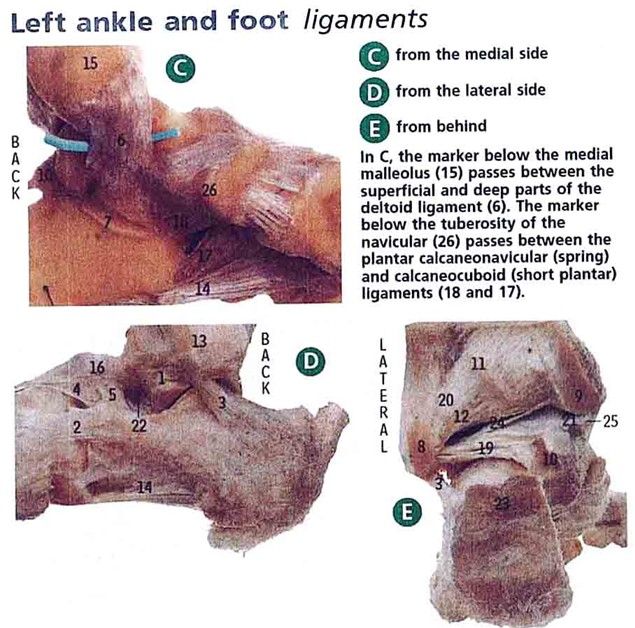

Inversion and eversion of footIdentify the Deltoid ligament, calcaneofibular ligament, posterior talofibular ligament:

Deltoid ligament (6)

Calcaneofibular ligament (3)

Posterior talofibular ligament (19)The dorsalis pedis pulse is found between the first two metatarsal bones.